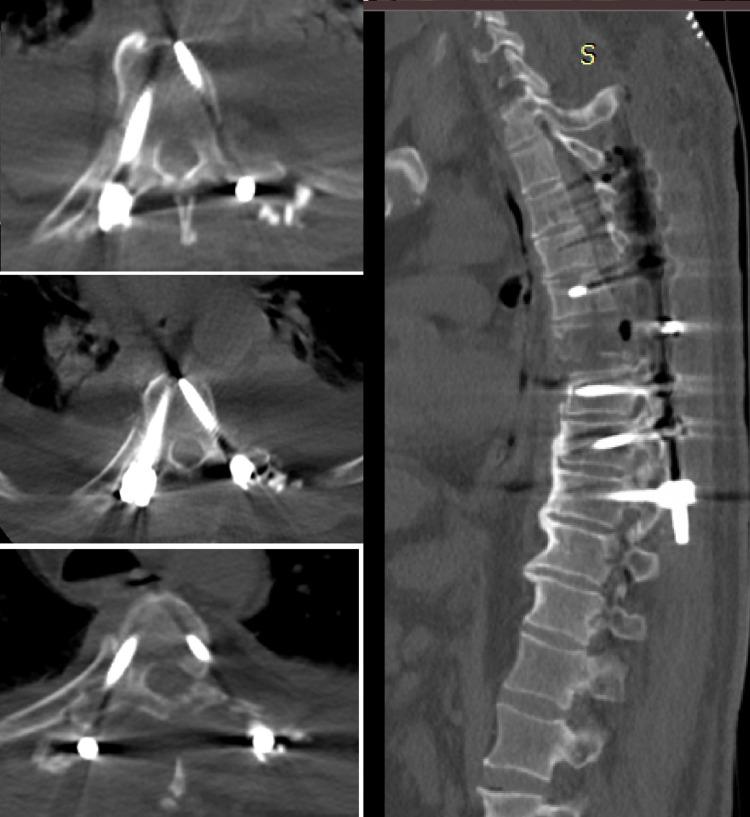

Background This study aims to compare the clinical results of patients with upper thoracic vertebral fractures treated with pedicle screw and posterior spinal fusion with preoperative surgical planning and 3-dimensional (3D) modeling and patients treated with freehand screws. Methods Fifty patients who underwent pedicle screw placement with a diagnosis of upper thoracic fracture between June 2018 and October 2020 were included in our study. Pedicle screws were used in 25 patients (group 1) after the planning was completed with the help of 3D preoperative printing and modeling. Pedicle screws were applied in 25 patients in the control group (group 2) using the freehand technique. Intraoperative bleeding amount, operation time, and correct screw placement data in both groups were recorded. Results The operation time was 134 ± 22 minutes for group 1 and 152 ± 38 minutes for group 2. The difference in operation times was found to be statistically significant (p < 0.05). Based on axial and sagittal reconstruction images, the accuracy rate of pedicle screw placement (grades 0 and 1) in group I was 96.6% compared to 83.6% in group II. The minor perforation rate (grade 1, <2 mm) was 5.8% in group I compared to 11.8% in group II. The moderate perforation rate (grade 2, 2-4 mm) was 3.4% in group I compared to 14% in group II. The severe perforation rate (grade 3, >4 mm) was 2.3% in group II; however, misplaced screws were not associated with neurological deficits. The difference in overall accuracy rates between the two groups was significant (p < 0.05). Conclusions For 3D models of upper thoracic pedicle screw insertion, guide plates can be produced inexpensively and individually. It provides a new method for the accurate placement of upper thoracic pedicle screws with high accuracy and secure use in screw insertion.

背景 本研究旨在比较采用术前手术规划和三维(3D)建模进行椎弓根螺钉及后路脊柱融合术治疗的上胸椎骨折患者与徒手置入螺钉治疗的患者的临床结果。方法 纳入2018年6月至2020年10月期间诊断为上胸椎骨折并接受椎弓根螺钉置入术的50例患者。25例患者(第1组)在术前3D打印和建模辅助完成规划后使用椎弓根螺钉。对照组(第2组)的25例患者采用徒手技术应用椎弓根螺钉。记录两组患者的术中出血量、手术时间和螺钉置入正确数据。结果 第1组的手术时间为134±22分钟,第2组为152±38分钟。发现手术时间差异具有统计学意义(p<0.05)。基于轴向和矢状面重建图像,第I组椎弓根螺钉置入准确率(0级和1级)为96.6%,而第II组为83.6%。第I组轻微穿孔率(1级,<2 mm)为5.8%,第II组为11.8%。第I组中度穿孔率(2级,2 - 4 mm)为3.4%,第II组为14%。第II组严重穿孔率(3级,>4 mm)为2.3%;然而,螺钉位置不当与神经功能缺损无关。两组总体准确率差异显著(p<0.05)。结论 对于上胸椎椎弓根螺钉置入的3D模型,可以廉价且个性化地制作导向板。它为上胸椎椎弓根螺钉的准确置入提供了一种新方法,在螺钉置入中具有高精度和安全使用性。